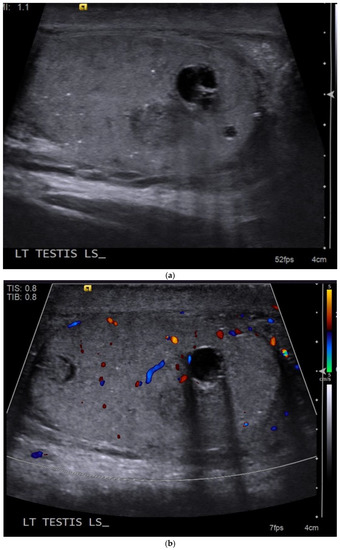

4.1. Seminomatous Germ Cell Tumour

| Seminomas | Homogenous and hypoechoic Well circumscribed Occasionally contain cystic components or calcifications |